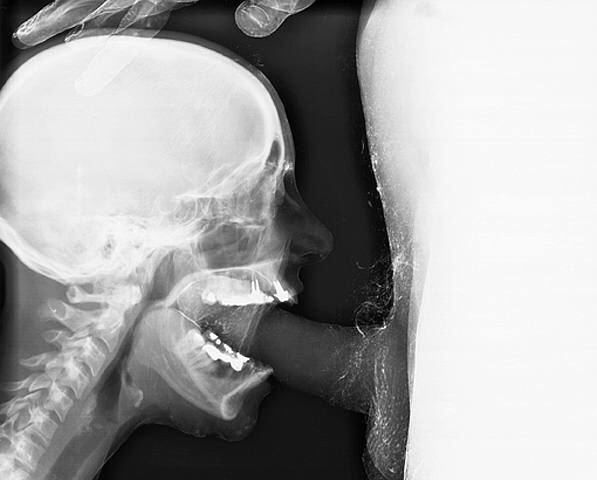

// погромист: хотел лось штонибудь про любовь